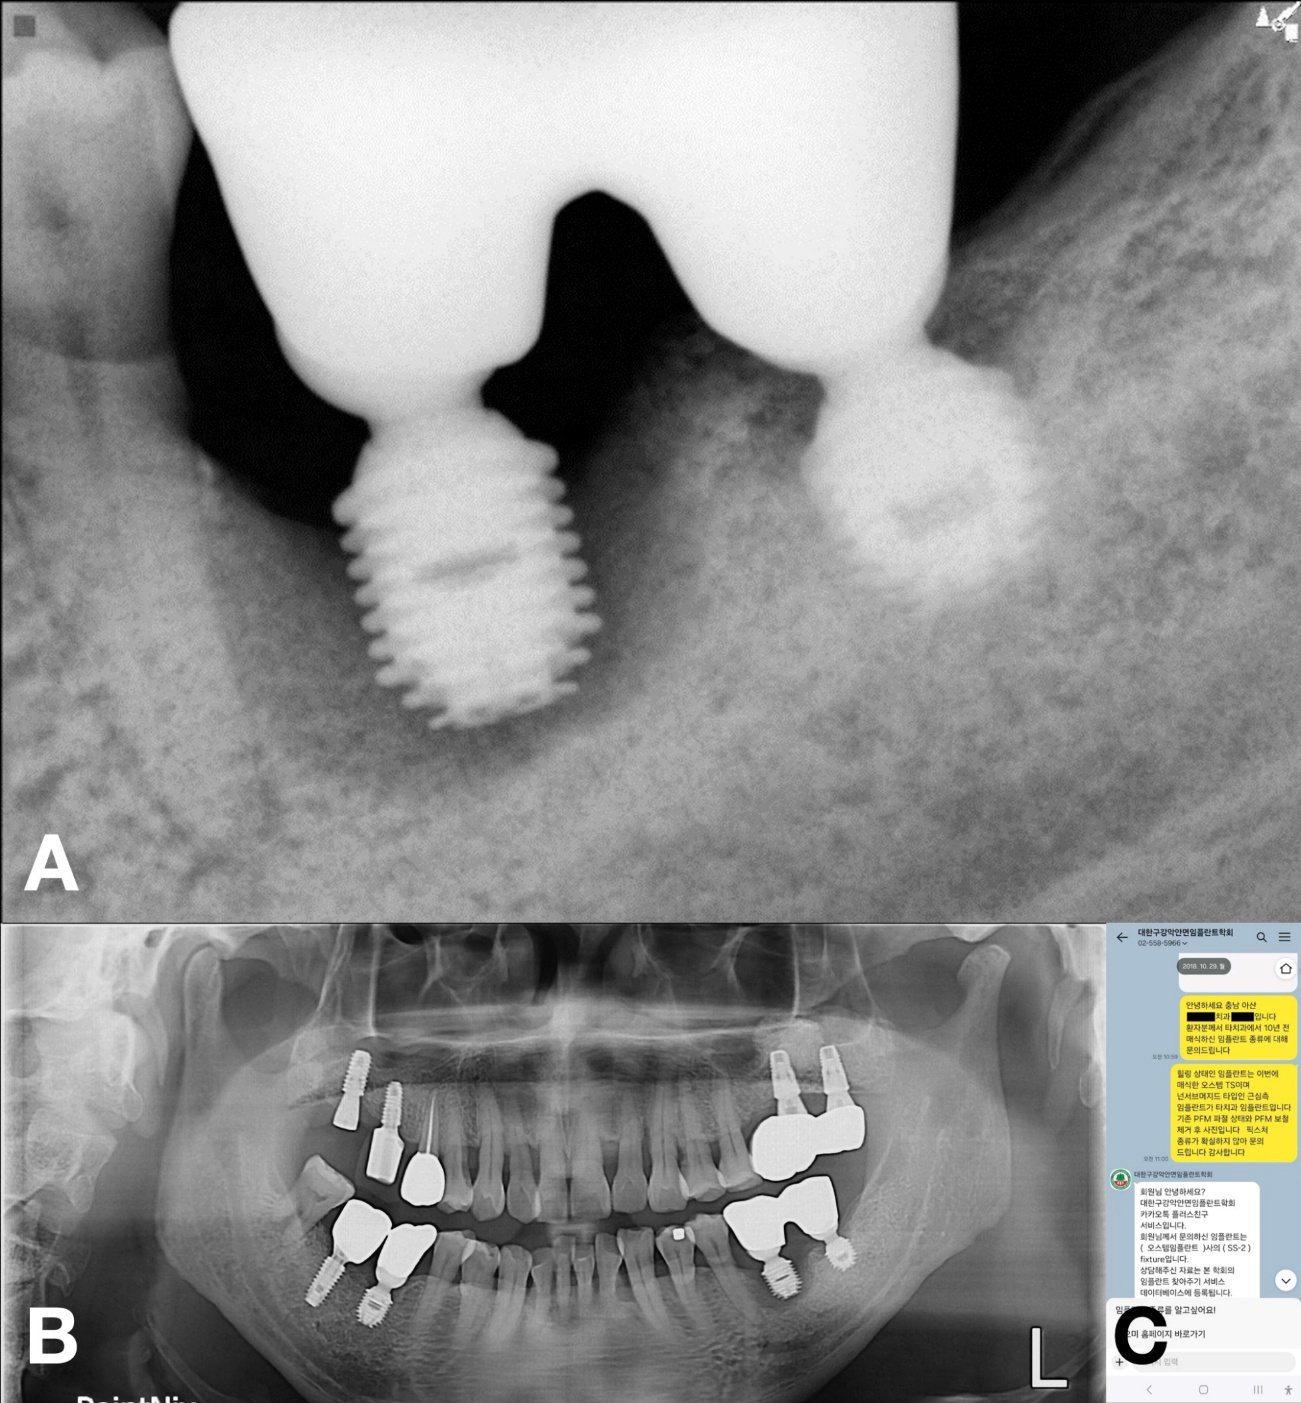

A 57-year-old male presented with suppuration and discomfort in the left mandibular molar region. Clinical and radiographic examinations revealed severe peri-implant inflammation and associated bone resorption around the fixture at site #36, while the implant at site 37 demonstrated stable peri-implant bone support.5 The two implants were restored with a splinted crown prosthesis (Fig. 1).

No documentation regarding the implants was available; therefore, the KAOMI implant finder service was consulted. The system identified the type of fixtures as Bicon implants (Bicon LLC; Boston, MA, USA). Based on this information, the manufacturer was contacted, and an appropriate abutment for #37 the fixture, intended for salvage, was procured (Fig. 2).